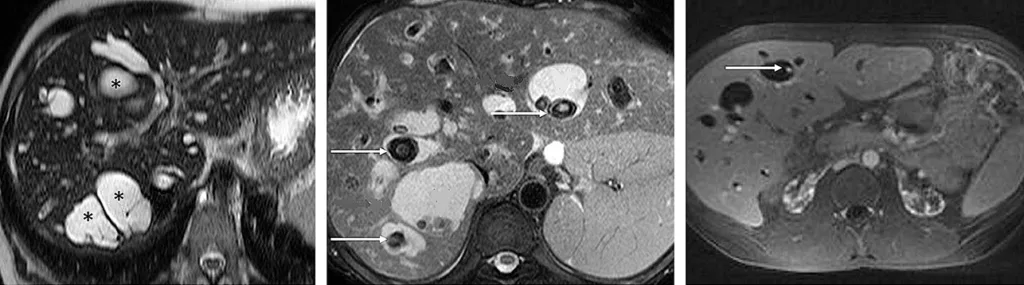

Le diagnostic positif de maladie de Caroli repose sur la cholangio-IRM. Celle-ci met en évidence de volumineuses dilatations kystiques des VBIH, en communication avec le reste de l’arbre biliaire (figure 7A). Il est fréquent de visualiser des calculs au sein des dilatations kystiques (figure 7B). Après injection de produit de contraste, il est classique de visualiser un vaisseau réhaussé (branche de la veine porte ou de l’artère hépatique) au sein de la dilatation kystique (figure 7C). Ce signe radiologique dit « central du point » (central dot sign), témoin d’une malformation de la plaque ductale, est pathognomique de la maladie de Caroli. Dans la maladie de Caroli isolée, les dilatations kystiques peuvent être localisées au niveau d’un lobe ou d’un segment hépatique, alors qu’elles sont généralement diffuses dans le cadre du syndrome de Caroli (tableau 1). Concernant le diagnostic de FHC, l’apport de l’imagerie est plus limité, mais permet d’évaluer la présence de signes radiologiques d’HTP (splénomégalie, voies de dérivations porto-systémiques). Il peut néanmoins exister des lésions biliaires associées à la FHC isolée sans syndrome de Caroli, à type de cholangite ou d’augmentation de volume de la vésicule biliaire (23).

Figure 7 : Visualisation par IRM hépatique de lésions caractéristiques de maladie de Caroli : dilatation kystiques (étoiles) des canaux biliaires intra-hépatiques (A) ; présence de calculs (flèches) au sein des dilatations kystiques biliaires (B) ; central dot sign : vaisseau réhaussé au sein d’une dilatation kystique (flèche) (C)